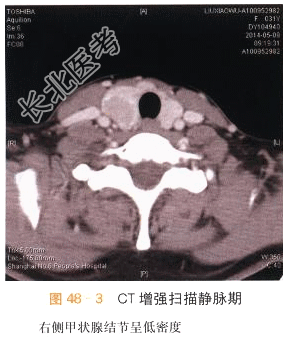

本案例CT扫描见右侧甲状腺增大,结节与正常甲状腺分界不清,呈低密度,见沙砾样钙化(见图48-1),增强后呈低度强化,甲状腺包膜不完整,(见图48-2~图48-4),结合超声检查,考虑甲状腺癌。